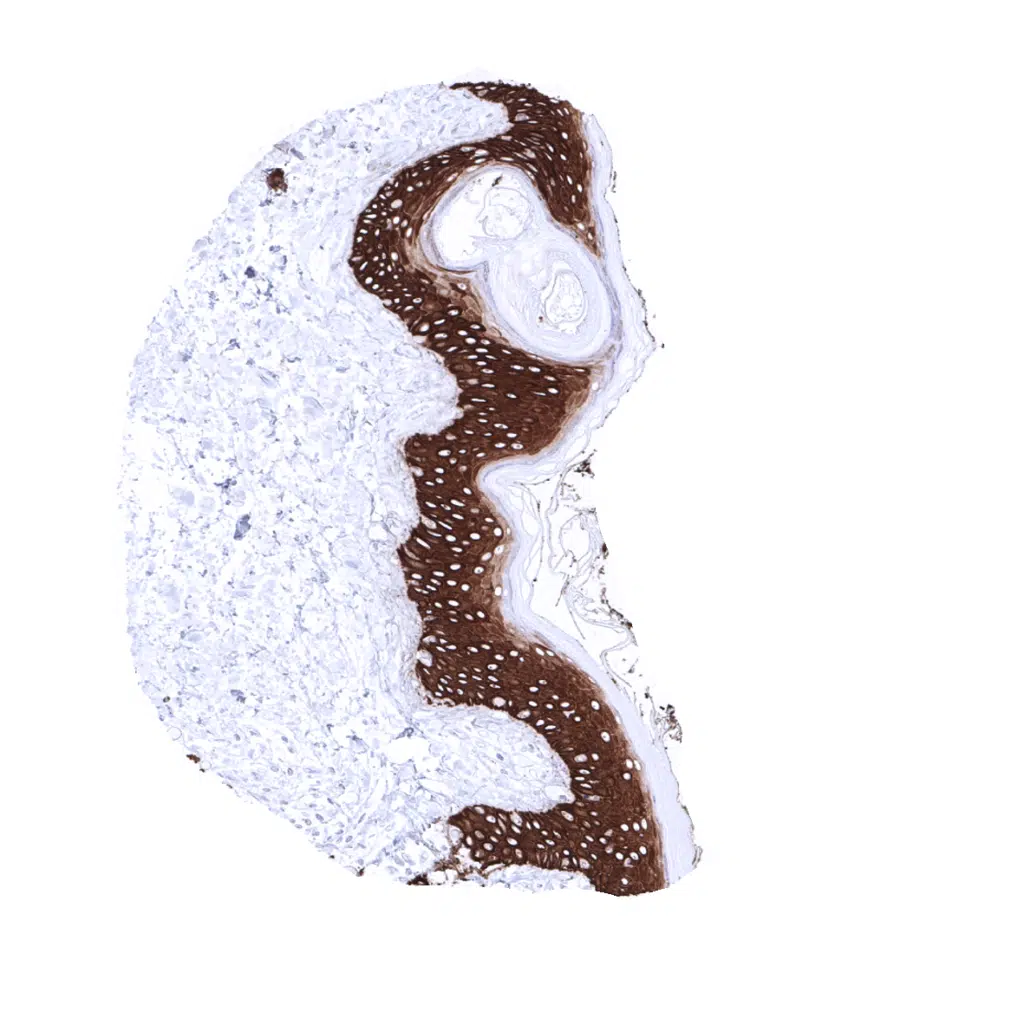

Skin